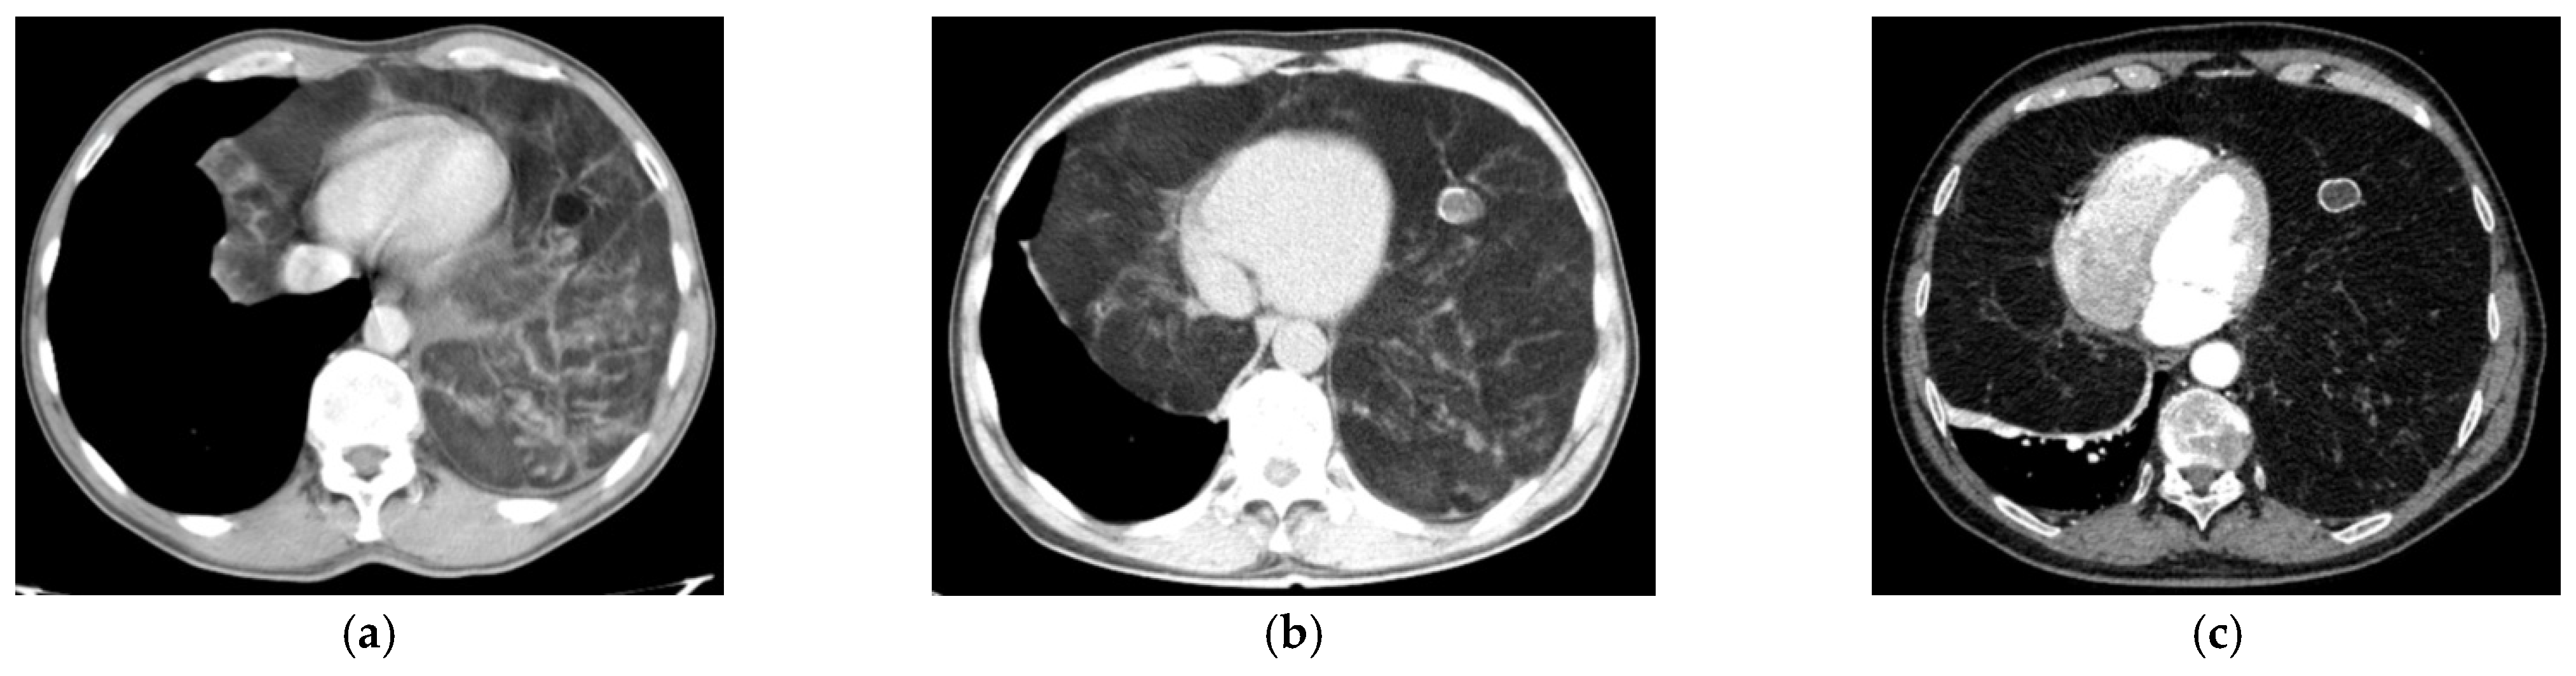

| CRC Stadium | Clinical-Radiological Findings |

| CRC 1 (minimal compression) |

|

| CRC 2 (moderate compression) |

| CRC 3 (“giant mediastinal tumor”) | |

| CRC 3A |

| CRC 3B |